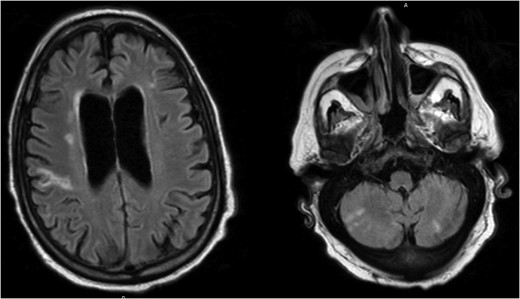

A 75-year-old male presented to clinic with a decline in mental status following 6 weeks of progressive weakness. His past medical history included hypertension, coronary artery disease, stable chronic lymphoid leukemia (CLL) and newly diagnosed congestive heart failure (CHF) with moderate aortic valve insufficiency seen on outpatient echocardiogram 3 weeks earlier. Vital signs were within normal limits, and physical exam revealed a non-focal neurologic examination, diastolic heart murmur and diffuse mild abdominal pain. Admission laboratories were notable for WBC of 18 500/mm3 (slightly increased above CLL baseline), with neutrophil predominance. Brain MRI (Fig. 1) and trans-esophageal echocardiography revealed multiple bilateral areas of restricted diffusion consistent with ischemic stroke, as well as a 2.2 cm aortic valve vegetation with severe aortic regurgitation, but no intra-cardiac abscess. Blood cultures confirmed Enterococcus faecalis endocarditis. Abdominal CT scan (Fig. 2) revealed an 8.1 cm splenic lesion consistent with splenic abscess.

Brain MRI demonstrating multiple bilateral areas of restricted diffusion consistent with ischemic stroke.